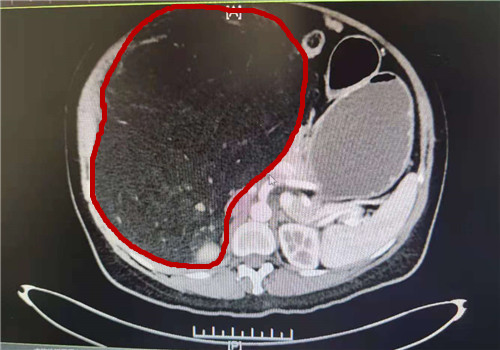

“住院之后,我们对她进行了进一步的检查,做了全腹部的增强CT。”泌尿外科徐光勇教授回忆说,CT结果显示该巨大包块最大截面约有274*192mm,来源于右肾,可能是血管平滑肌脂肪瘤。

术前CT图,红圈部位为肿瘤

在患者右侧腹直肌处切开长约25cm的切口,逐层进入腹腔后,一个巨大的肿瘤呈现在医生们的眼前。“肿瘤在腹腔右边,看起来大约20*30cm。因为太大,把旁边的脏器都挤压到左边去了。”徐光勇教授说。